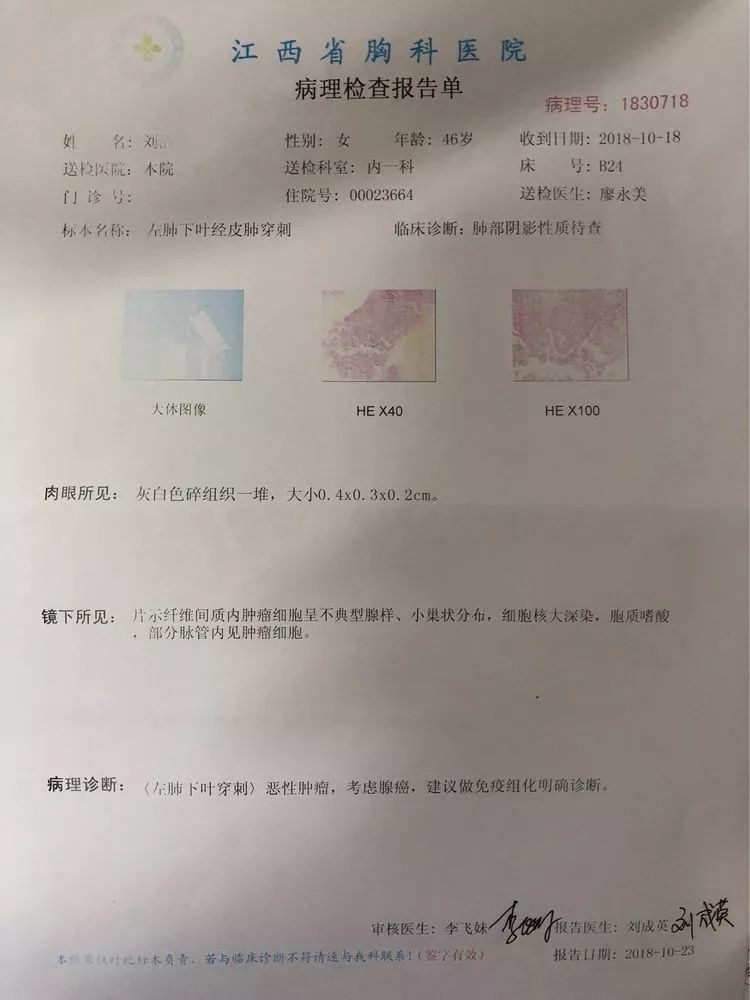

第二例 46岁的刘阿姨既往有肺结核病史,规则治疗,三月前出现胸背部隐痛,在其他医院胸片检查考虑陈旧性结核,但她一直未在意,之后由于症状一直没有缓解便选择来省胸科医院就诊,经检查,胸部CT两上肺确实有陈旧性病兆,但左下背段有一个1.5厘米左右的结节。

像这种肺外周的结节一般的气管镜做不到,所以医生选择使用穿刺活检。

穿刺活检后送至病理科,待报告出来后显示腺癌,可惜,癌细胞已经向肋骨和胸椎多处转移,患者已经失去了手术机会。